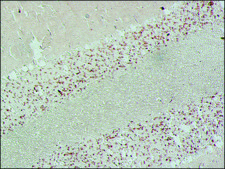

immunohistochemistry (formalin-fixed, paraffin-embedded sections): suitable, immunohistochemistry (frozen sections): 1:200 using rat cerebellum, indirect ELISA: suitable, western blot: suitable

Synaptophysin (SYP) is an integral membrane glycoprotein of 38,000 Da and it has four membrane-spanning domains. Synaptophysin is localized to neurons, neuromuscular junctions, paraganglia cells, hypophysis, pancreatic islet cells, and adrenal cells. SYP gene is mapped to human chromosome Xp11.23. Monoclonal Anti-Synaptophysin (mouse IgG1 isotype) is derived from the hybridoma produced by the fusion of mouse myeloma cells and splenocytes from an immunized mouse.

Labels synaptophysin in neurons, neuromuscular junctions, benign and malignant neural tumors, paraganglia cells, hypophysis, pancreatic islet cells, and adrenal cells.

Synaptophysin participates in calcium dependent exocytosis. The antibody detects synaptophysin in many types of benign and malignant neural and epithelial neuroendocrine neoplasms. It is widely used as a potential marker to study the circulation of synapses in the brain and to discover the basic features of the life cycle of synaptic vesicles (SVs).